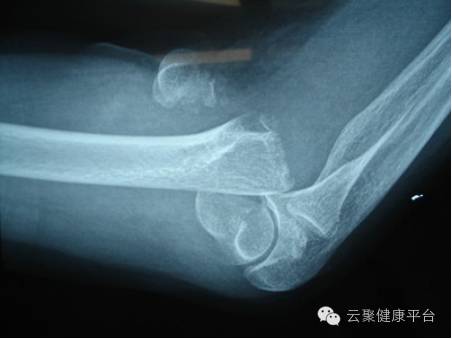

1、外伤骨头——粗看X光片、细看CT

各种外伤,如果怀疑伤到了骨头,优先选择X光照片,检查结果快速易得。若要进一步观察,可以选择CT。超声、核磁对于骨皮质等看不大清,一般不选择。